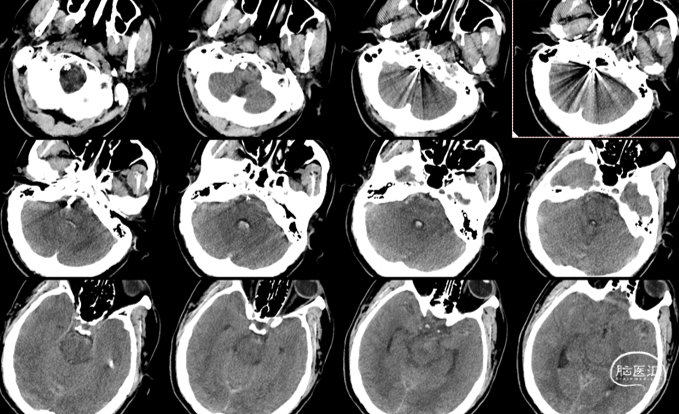

头颅CT:

蛛网膜下腔出血,以脑干前方密度较高,

并逆流入四脑室。

术后检查:次日CT

术后14天,头颅CT示蛛网膜下腔出血完全吸收,头痛缓解,痊愈出院。